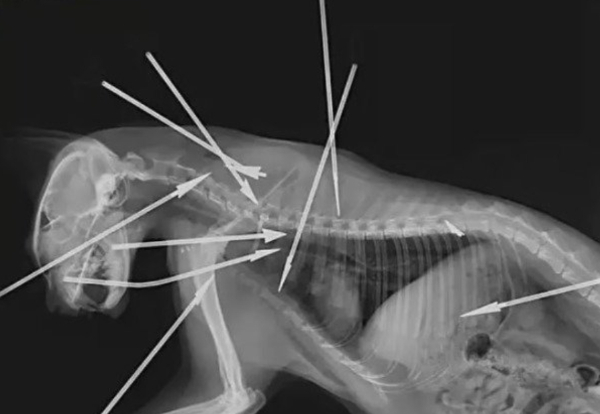

중국 누리꾼들은 조속히 관련 법규를 마련할 것을 촉구하는 분위기다. 사진은 다트를 맞은 고양이의 X-레이 모습. /사진=바이두 캡처

28일(이하 현지시각) 홍콩 사우스차이나모닝포스트(SCMP)에 따르면 최근 동물보호 운동가들이 중국 동부 저장성 항저우 주택가에서 머리와 가슴 등에 10개의 강철 다트를 맞고 신음하던 유기묘를 발견했다. 동물 병원으로 고양이를 급히 옮기고 약 90분간 수술했으나 고양이는 결국 죽었다.